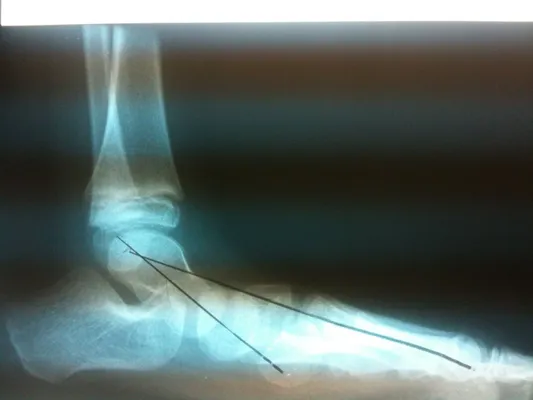

Below are x-rays of a foot pre-operatively (left) where the black line indicates and plantarflexed (downward directed) talus bone and post-surgical repair with a subtalar joint implant and lenthening of the calf muscle which allows the calcaneus (heel bone) to set underneath the talus and the implant keeps the talus from subluxing off the calcaneus and now the talus is more inline with the front of the foot (right).

Preop flatfoot surgery on Left foot and post Achilles lengthening with subtalar implant right (Below)